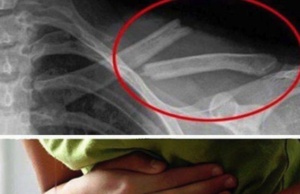

Otrava asta îţi distruge oasele! O consumi în fiecare zi fără...

Ori de câte ori ieşi în oraş, sigur serveşti şi o băutură acidulată. Cu aromă de mere, struguri ori piersici, o savurezi aproape pe...